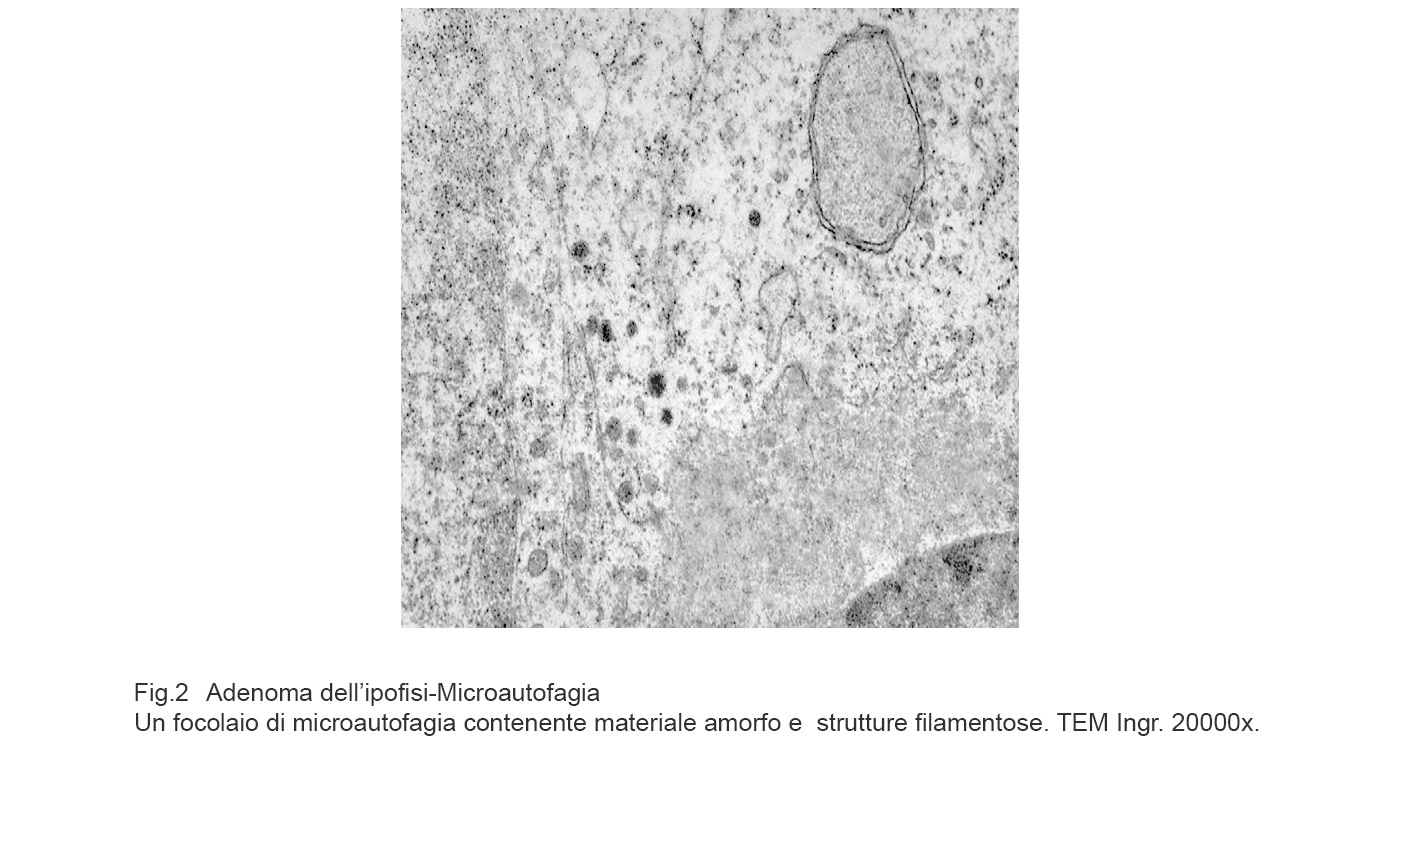

MICROAUTOFAGIA

I focolai di microautofagia si ritrovano frequentemente commisti a mitocondri disfunzionali e a reticolo- endoplasmatico in stato di stress.

Essi sono di piccole dimensioni, appaiono come vescicole, delimitate da una membrana a doppio strato, immerse nel citosol e

ricolme di materiale amorfo oppure di materiale amorfo commisto a frammenti filamentosi.

Fig.2